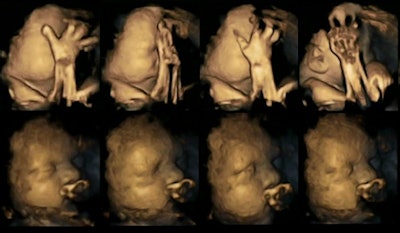

In a small study published in Acta Paediatrica, researchers in the U.K. used 4D ultrasound to detect changes in facial movements of fetuses that could reflect the effect of maternal smoking.

Researchers at Durham and Lancaster universities, led by Dr. Nadja Reissland of Durham, performed 80 4D ultrasound scans on 20 fetuses to assess subtle mouth and touch movements. The scans were acquired at four different intervals between 24 and 36 weeks of pregnancy (Acta Paediatr, March 12, 2015).

The researchers tracked mouth movements on the scans, and they found a statistically significant difference between the fetuses carried by the smoking women versus those of the nonsmokers (p < 0.02). The fetuses of the smoking women showed a higher rate of movements than the normal declining rate expected during pregnancy, and the differences between the smoking and nonsmoking groups widened as the pregnancies progressed.